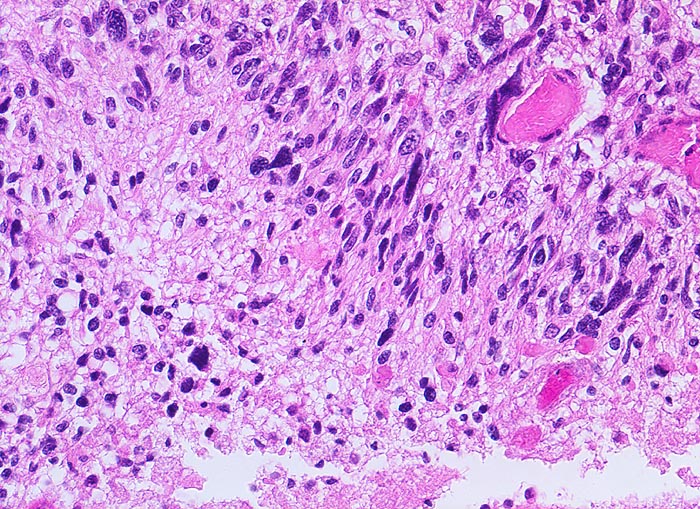

PathoPic – image database / PathoPic ID 5200 - Glioblastoma multiforme (WHO IV)

Glioblastoma multiforme (WHO IV)

Hirn temporal

Parallele Ausrichtung der Tumorzellen zueinander und senkrecht zur Tumornekrose links unten im Bild.

Seit zwei Monaten zunehmende Persönlichkeitsveränderungen, Kopfschmerzen und progrediente fokal neurologische Zeichen.

Histologie

200